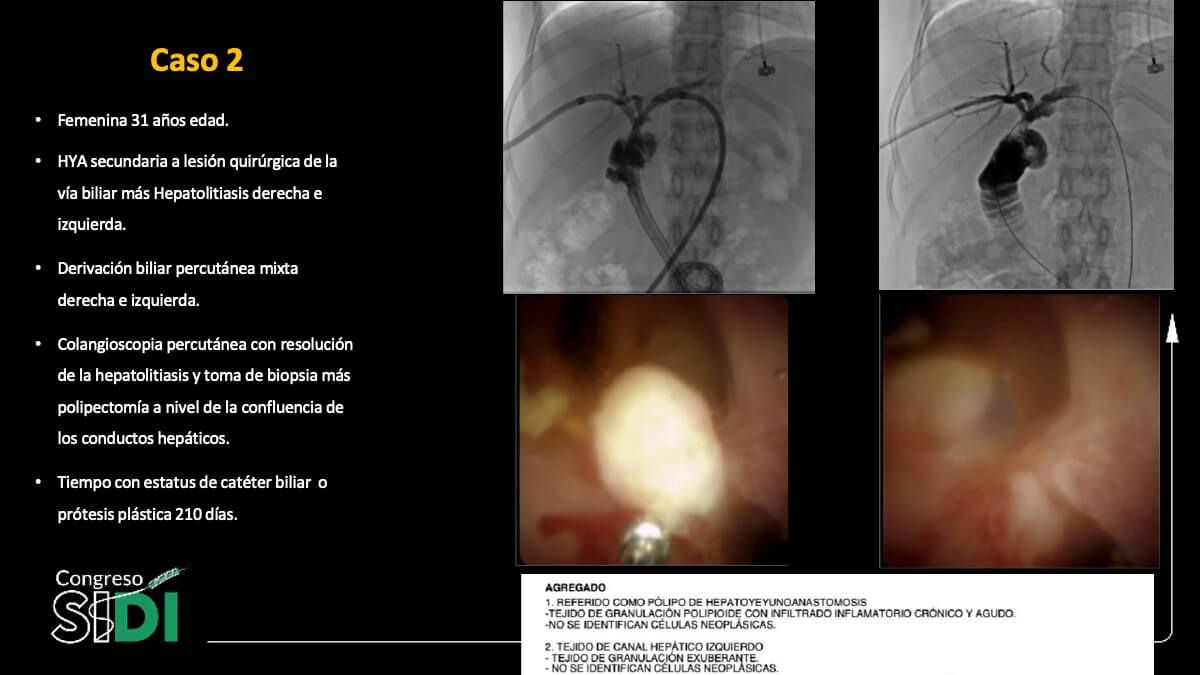

Cambios tisulares en el epitelio biliar inducidos por prótesis plásticas: Evidencia colangioscópica e histológica

Dr. Carlos Saldívar